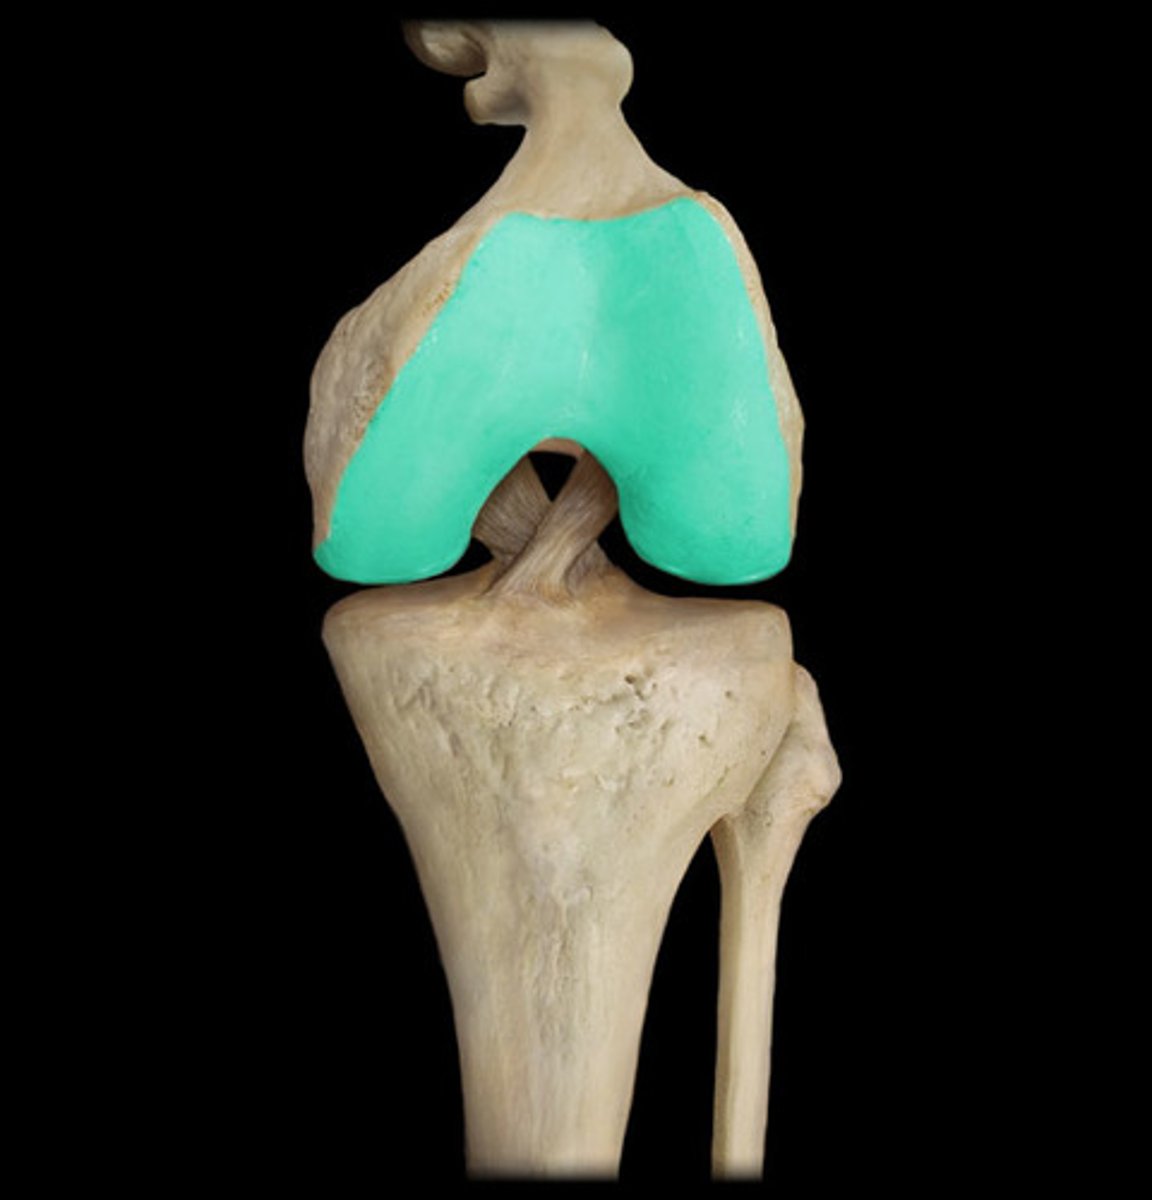

joints most commonly affected include

hips and knees

cartilage

osteoarthritis (image)